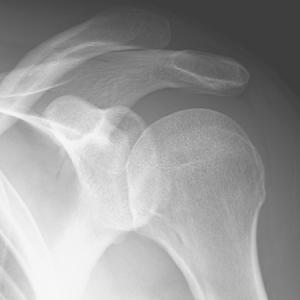

Schulter

Die Schultereckgelenksverletzung ist eine der häufigsten Verletzungen bei Stürzen direkt auf die Schulter oder im Kontaktsport. Das betroffene Gelenk verbindet das Schlüsselbein mit einem knöchernen Fortsatz des Schulterblattes. Dieses ist durch mehrere Bänder sowie eine Kapsel gesichert. Je nachdem wie viele und welche Bänder verletzt sind entsteht eine Instabilität. Die Schmerzen sind am Anfang deutlich einschränkend.

Bei einem auskugeln der Schulter kommt es oft zu entscheidenden Begleitverletzungen. Meistens ist die stabilisierende Gelenklippe – auch Labrum genannt – abgerissen. Je nach Größe der abgelösten Strecke sowie des Patientenalters, persönliche Ansprüche und eventueller Begleitverletzungen, kann sowohl eine nichtoperative Therapie als auch eine Stabilisierungsoperation erfolgen.

Oft besteht ein Missverhältnis der schultergelenszentrierenden Muskeln und ein dadurch verursachtes höhertreten des Oberarmkopfes unter das knöcherne Schulterdach. Auch ein Knochensporn kann zu den Schmerzen beitragen. In diesem engen Raum laufen Sehen der Rotatorenmanschette sowie die Bizepssehne und mindestens ein Schleimbeutel. Hier kann es zu einem Einklemmen der genannten Strukturen kommen.